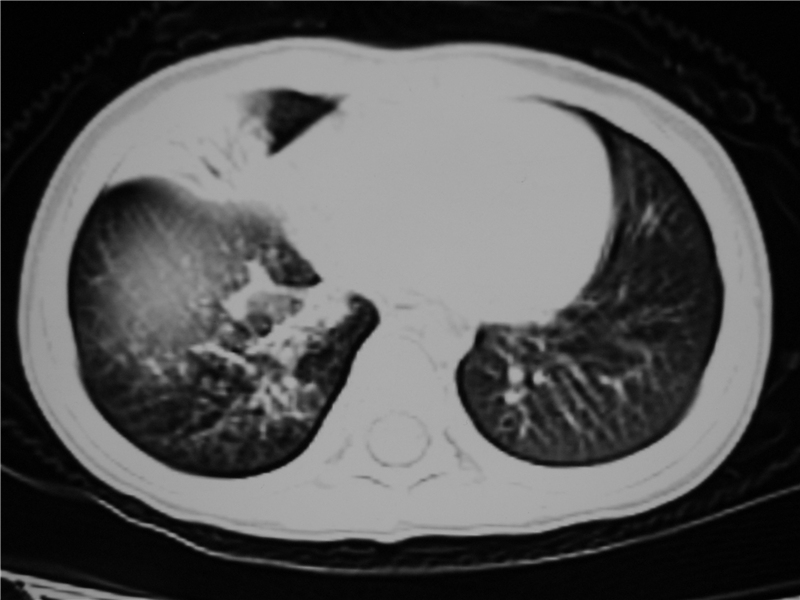

右肺中叶及下叶内段大片实变密度增高影,可见支气管气象,肺炎.

摄吸气及呼气相对比片,本例为有肺中叶阻塞性炎症、不张,右肺下叶阻塞性炎症。

1)右肺炎症并右肺中叶肺不张,右肺上叶充气不良。2)右侧支气管异物不排除。

结合病史,考虑气管异物所致。

结合临床考虑支气管异物并阻塞性肺炎、肺不张。

右肺中,下叶炎症结合病史不除外异物阻塞支气管